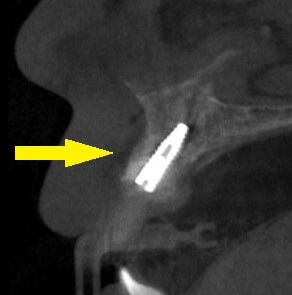

そこで、インプラント埋入と同時に唇の側に人工骨を補填するという骨造成法を併用し、本日、埋入を行いました。

下の写真下段左が手術前のCT、右が手術後のCTです。インプラントの唇の側に、白く人工骨が写っています。